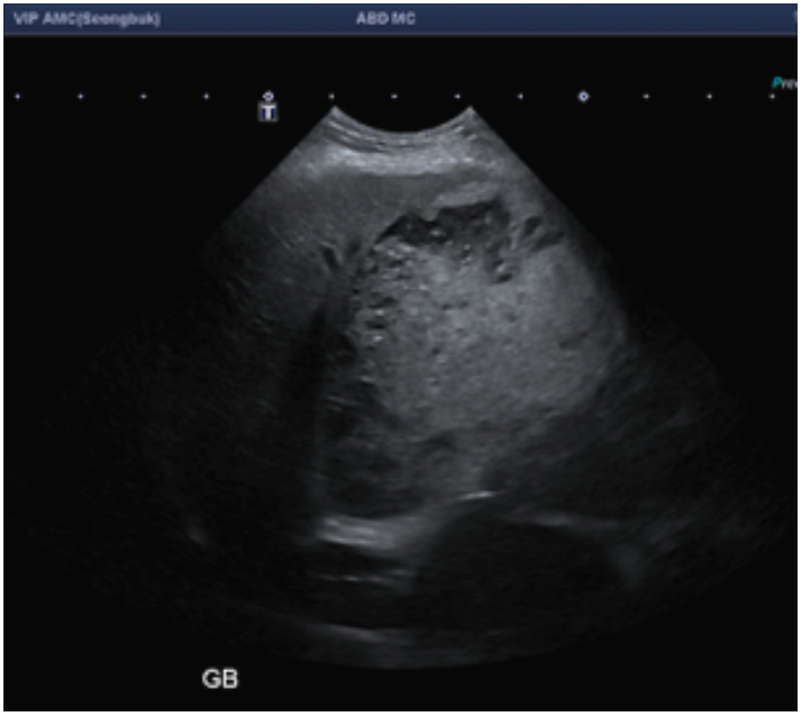

본원에서 다시 평가를 했을 때에도 담낭을 메우고 있는 물질의 양상은 Type 2에 해당하는 비교적 초기 상태이긴 하지만 담낭이 굉장히 팽만된 상태였고, 이런 흐름이 지속되어 간다면 주변으로 염증을 유발하여 간에도 더 큰 영향을 줄 수 있고 기력 저하, 식욕 부진의 증상이 나타날 수 있는 상태였습니다.

(본원에서 검사한 초음파 사진. 담낭 슬러지가 담낭 전체를 가득 메우고 있고, 변연부에 점액성 변화를 보이는 물질들이 생성되어 가는 중. 담낭점액종 Type 2. ▲)